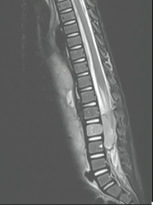

2岁 女孩,右腹部肿块

| 脊柱两侧病变活检 |

病理:神经母细胞瘤